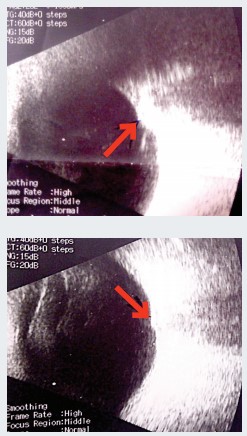

Эхоскопия. ОD — умеренная деструкция стекловидного тела, задняя гиалоидная мембрана (ЗГМ) частично отслоена, оболочки прилежат, в ДЗН гиперэхогенное включение (друзы?). OS — умеренная деструкция стекловидного тела, ЗГМ частично отслоена, оболочки прилежат, в ДЗН гиперэхогенное включение, ДЗН проминирует в стекловидное тело (см. рис. 1).

Осмотр глазного дна с фундус-линзой. OS — в основании ДЗН округлое проминирующее пигментированное (меланоцитома?) образование, границы и ткань ДЗН не определяются, мелкая капиллярная сеть по поверхности ДЗН, гиперпапиллярно отек нейроэпителия сетчатки (НЭС). Окклюзия артерий по верхневисочной и носовой аркадам, в зоне верхневисочной и верхненосовой аркад молочно-белый отек сетчатки с захватом верхней части фовеа. Сетчатка прилежит (см. рис. 2). Лазерная коагуляция не показана. Рекомендована консультация онкоофтальмолога.